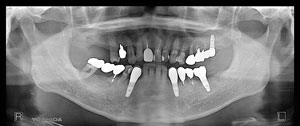

@@R.S‚³‚ñ@56Î —«  ‘åŠw‹³Žö @Žèp“ú@‚Q‚O‚O‚W”N ‚QŒŽ ‚X“úi“yj@㉺Š{  ƒm[ƒxƒ‹ƒKƒCƒhŽg—p@Ö¬“à’ÁÖ@•¹—p@@@

@@@@@ãŠ{  All on ‚U@‘¦Žž‰Ád@@

@@@@@@@@@@@@@ Rpl Tapered Rp  ‚P‚O mm(‚U–{)

@@@@@‰ºŠ{¶‰E@‘¦Žž‰Ád@ ‚R Unit Bridge@

@@@@@@@@@@@ @Rpl Tapered Rp  ‚P‚O mm(‚S–{)@@–ƒWƒ‹ƒRƒjƒAƒNƒ‰ƒEƒ“‚ÅÅI•â’Ô